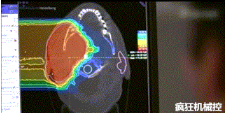

▲360°重離子治療一體機治療腫瘤

360°重離子治療一體可從任何角度用重離子(碳,氦,氧)和質(zhì)子(氫)照射腫瘤。此外,基于機器人的治療臺可以通過六種方式進行調(diào)整。

光柵掃描被集成到360°重離子治療一體機中,這種極其精確的照射方法以毫米為單位掃描腫瘤,可以保護健康組織且只治療腫瘤區(qū)域。

特別是腫瘤在高度輻射敏感位置或者諸如視神經(jīng)附近的復(fù)雜位置,可以通過選擇最佳射束入射角來減小這些器官的損傷。